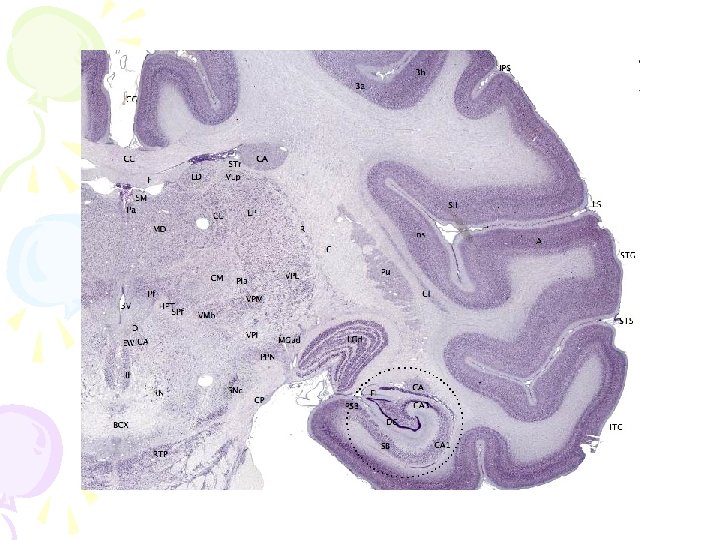

Forebrain • thoughts and reason • 5 main regions: – Thalamus – Hypothalamus – Hippocampus – Amygdala – The Cerebral Cortex

Limbic System

Limbic System • includes the thalamus, hypothalamus, hippocampus, and amygdala • “emotional brain” –helps regulate memory, aggression, fear, hunger, and thirst

Hippocampus • memory processing

Amygdala • emotions, especially those of aggression, rage, and fear • In stressful situations, where teens make some of their decisions